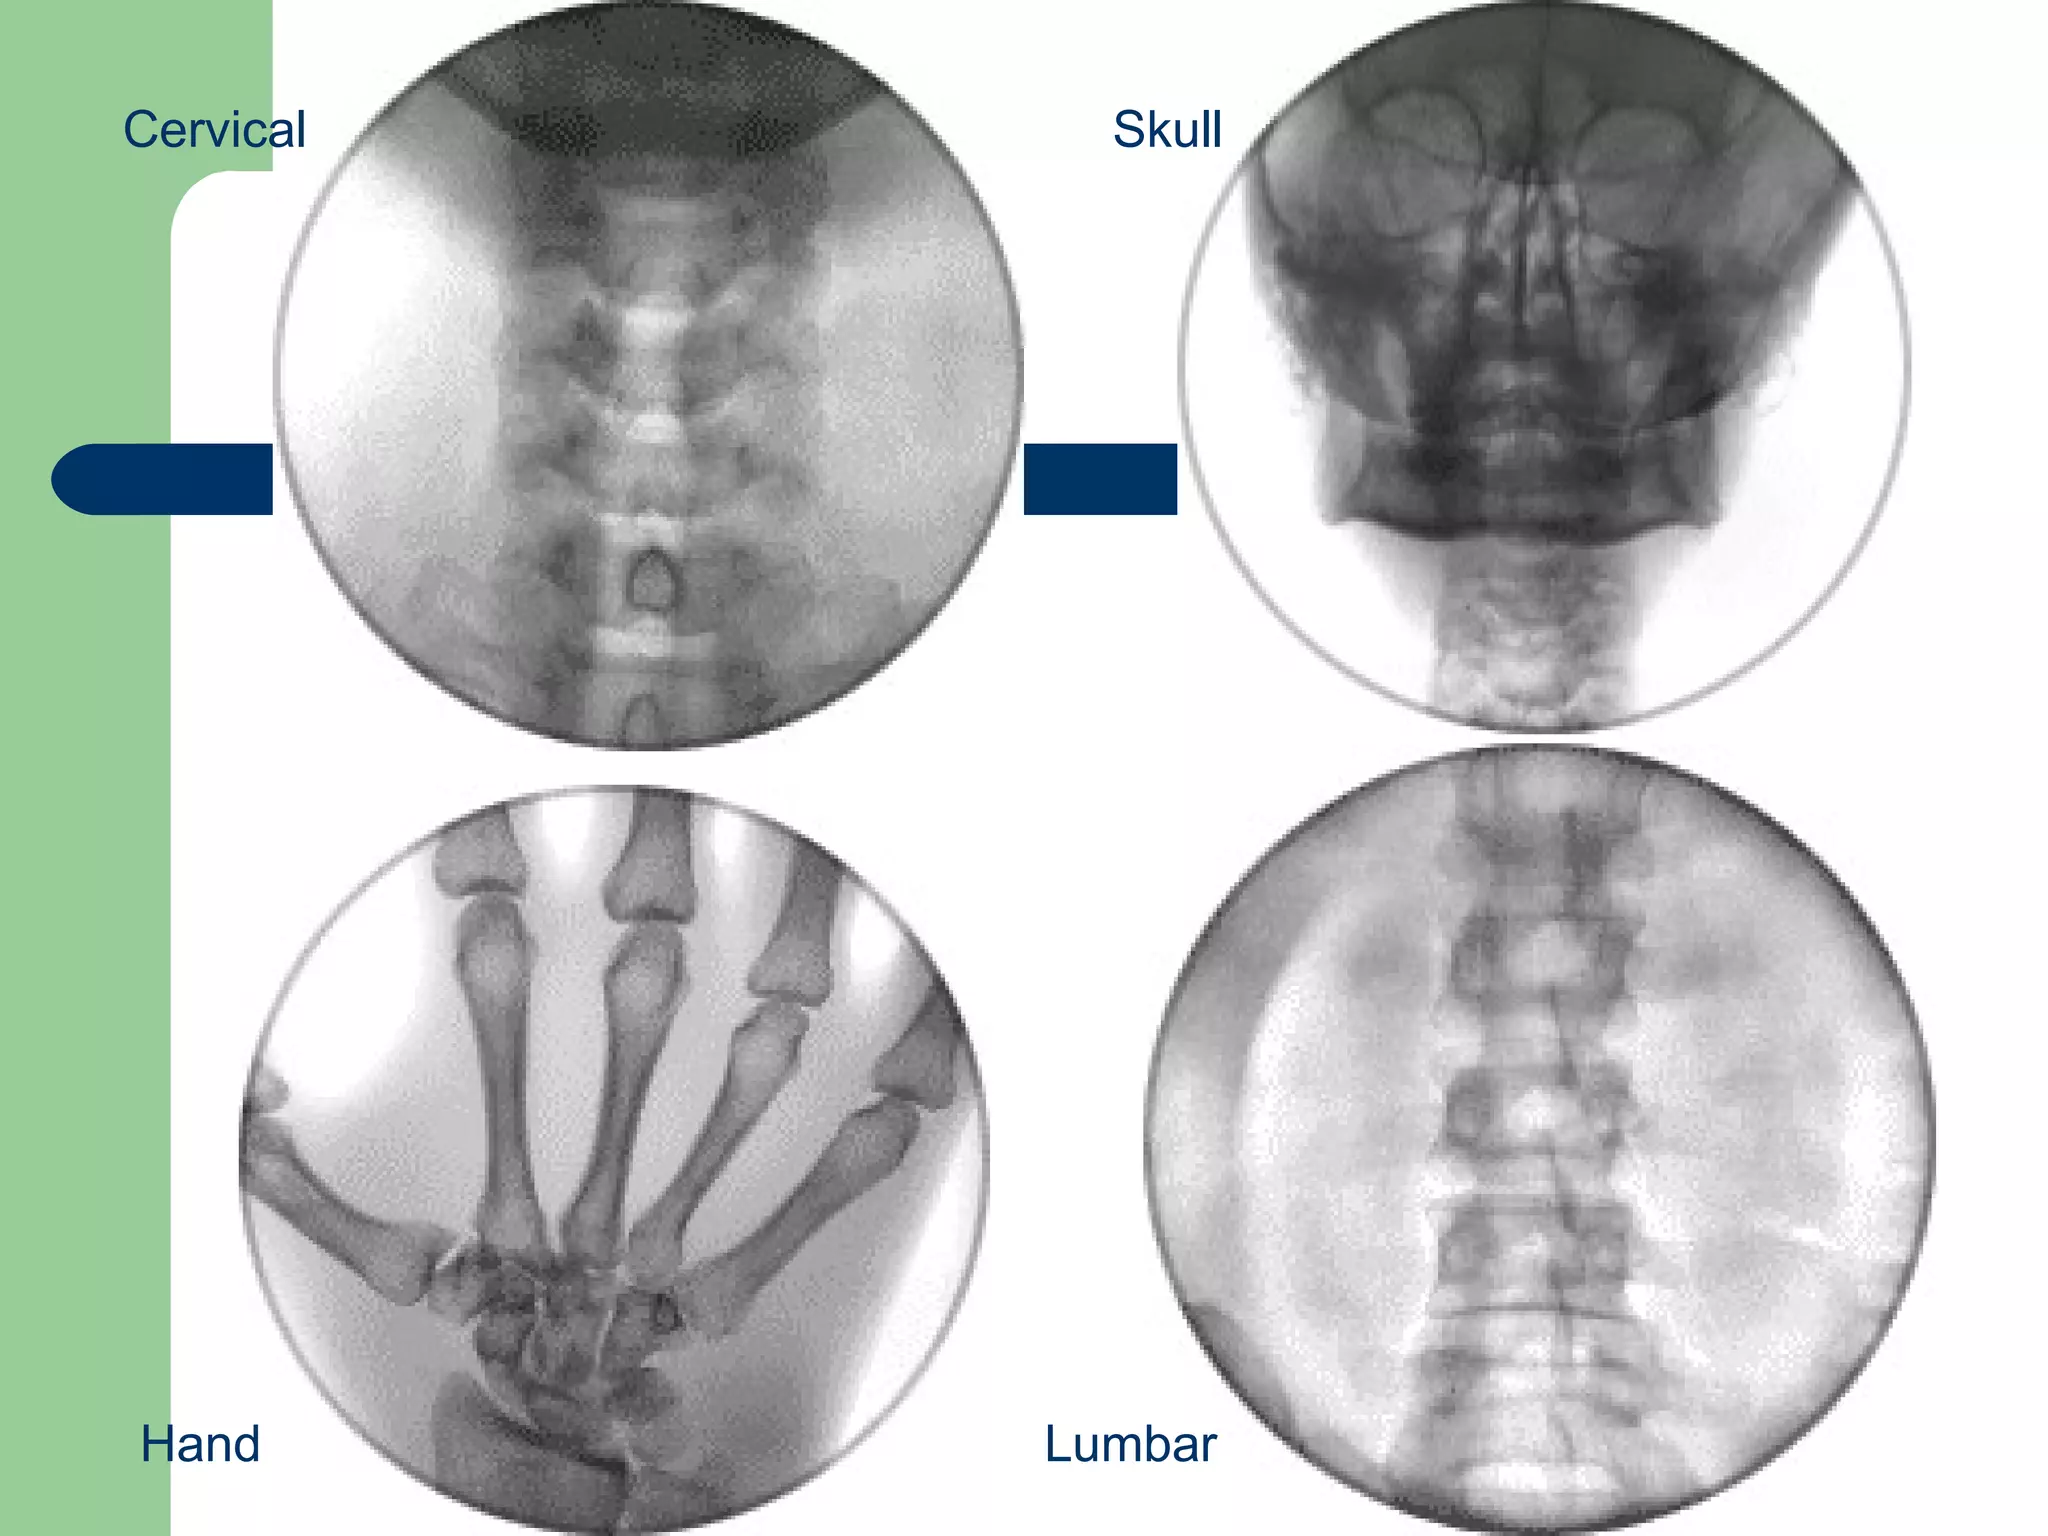

Cervical Hand Lumbar Skull

Our Breakthrough Technology We have developed a breakthrough medical technology that will produce 3D medical diagnostic images in real time, giving us enormous potential to contribute to the improvement of healthcare.  Healthcare workers will be able to instantly view 3D, high-resolution images of virtually any part of the human body.  Our 3D images are instantly constructed using high-resolution fluoroscopy and can be used as real time references for any current or new medical procedures in which multiple frames of reference are required to perform those procedures on or in the human body.

Our Technology With Imaging 3 technology, physicians are able to view depth and direction simultaneously.